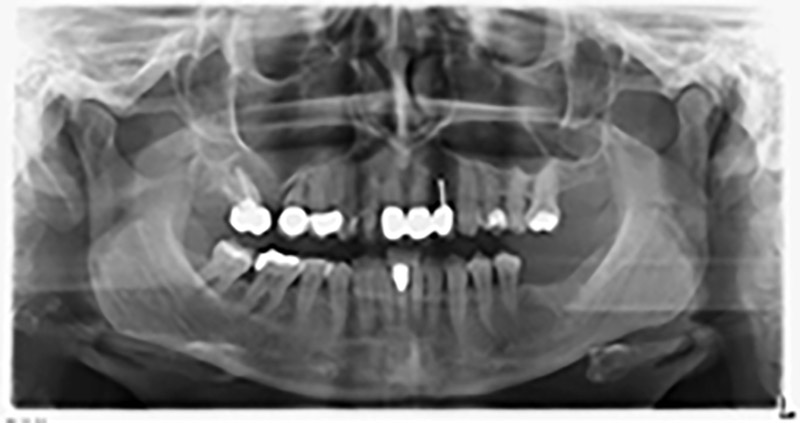

Unos seis meses después de la extracción de las piezas 16 y 14 se realizó una tomografía digital de volúmenes (DVT, Planmeca) para realizar una planificación adecuada y reducir los riesgos al mínimo. En este punto se constató que el hueso no se había regenerado en la cantidad deseada (figuras 2 a 7).

Con el fin de garantizar una restauración fija en al menos dos implantes, era preciso realizar una elevación del suelo del seno maxilar, tanto en la región 16 como en la región 14. Como en este caso la oferta de hueso residual era extremadamente reducida, fue preciso realizar una retirada ósea relativamente grande. Los procedimientos de retirada ósea grande son invasivos y, además, están asociados a una mayor morbilidad del paciente, llevan más tiempo y resultan más costosos. También es más difícil prever los resultados del tratamiento y el riesgo de fracaso es mayor. Teniendo como telón de fondo estas desventajas, la paciente recibió información sobre la posibilidad de utilizar una alternativa extraíble, pero ella la rechazó firmemente.

Para limitar el aumento a la región 14, se mantuvieron conversaciones con la paciente y se acordó una incorporación oblicua del implante 16 hacia la zona dorso-craneal (figura 8).